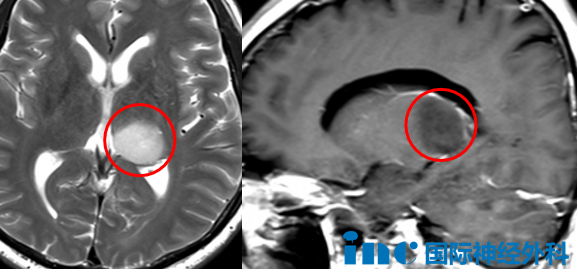

"上天派遣巴教授前来救助,我们还有什么可担忧的?"作为本次行程的首例手术,54岁左侧丘脑-海马占位患者王先生及其家属在经历半年多的艰难决策后,充满信心。巴教授已为其制定详细术前计划,并将于明日亲自执刀完成这台示范手术。教授的到访,仿佛寒冬中的一缕阳光,为这个家庭带来了新生的希望。

巴教授通过详细分析每一份影像资料,综合考虑患者的具体病情和功能状况,采用个体化方法评估每例手术的可行性、潜在风险及预期效果,为患者提供明确指导。